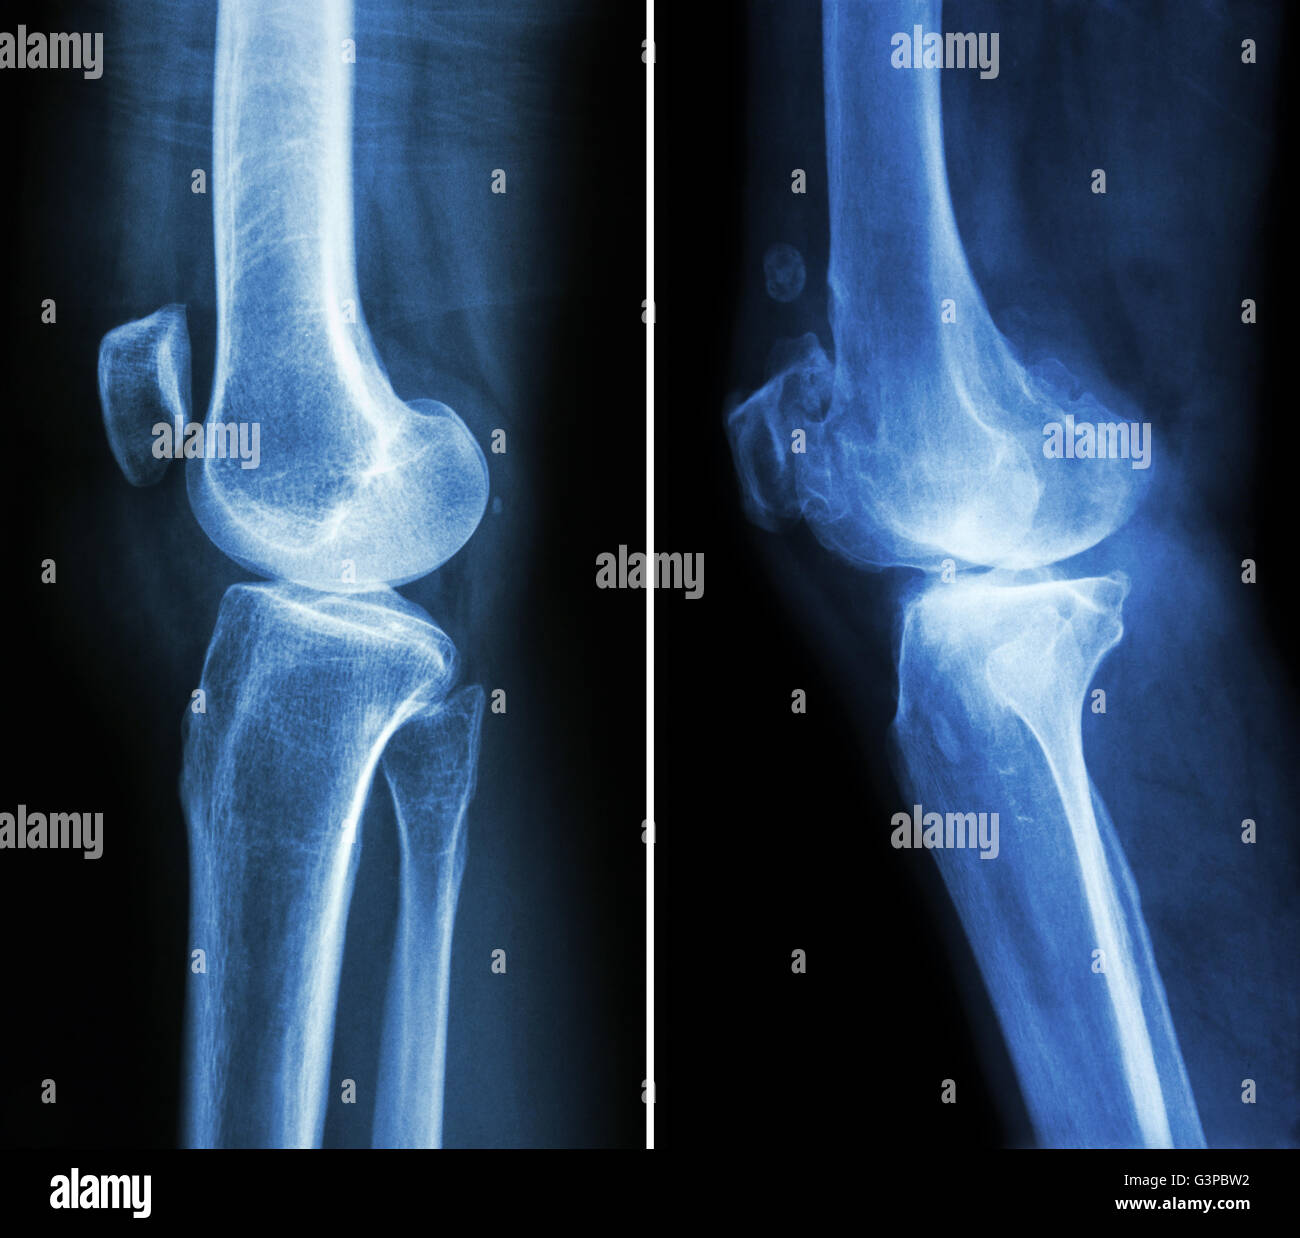

Film X-ray montrent l'articulation du genou normal(AP/latéral) Banque D'Imageshttps://www.alamyimages.fr/image-license-details/?v=1https://www.alamyimages.fr/photo-image-film-x-ray-montrent-l-articulation-du-genou-normal-ap-lateral-77387023.html

Film X-ray montrent l'articulation du genou normal(AP/latéral) Banque D'Imageshttps://www.alamyimages.fr/image-license-details/?v=1https://www.alamyimages.fr/photo-image-film-x-ray-montrent-l-articulation-du-genou-normal-ap-lateral-77387023.htmlRFEDW7X7–Film X-ray montrent l'articulation du genou normal(AP/latéral)